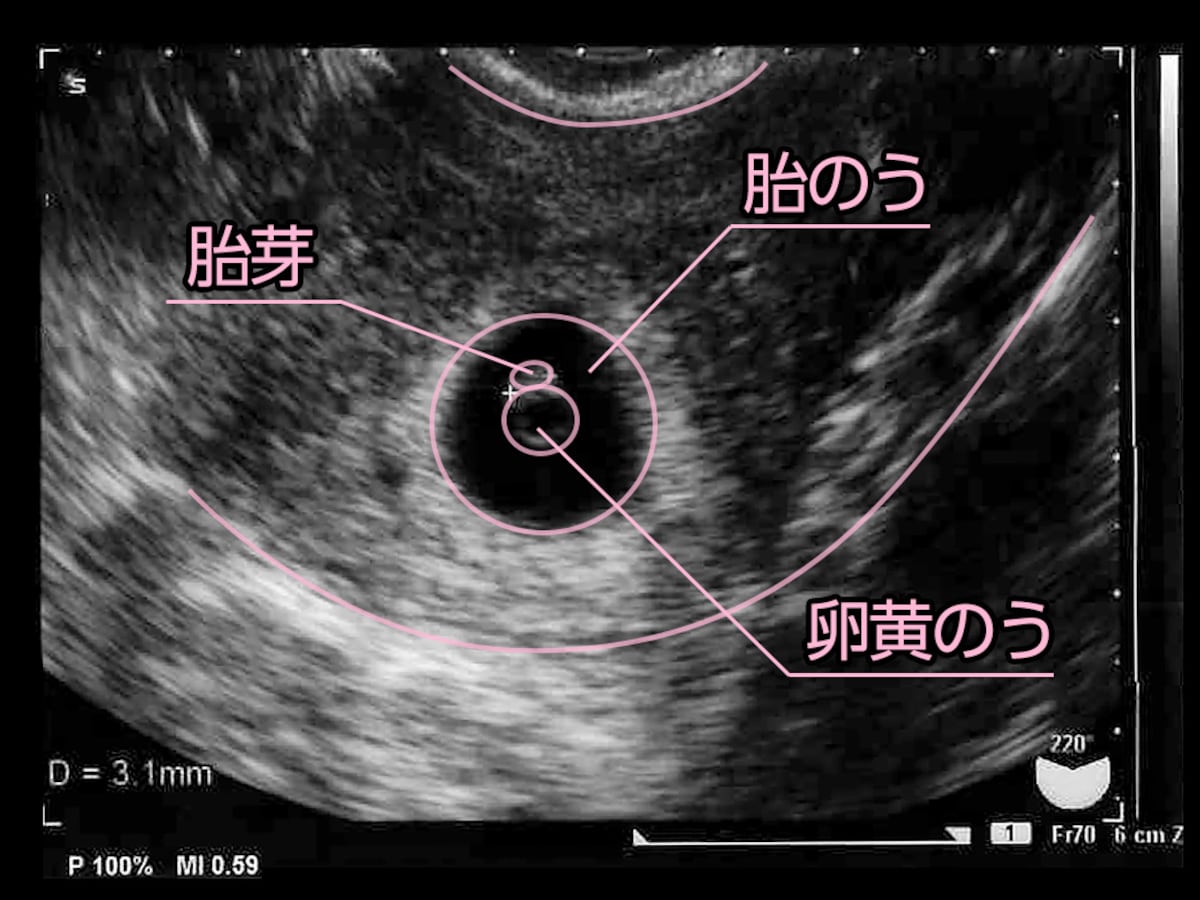

胎嚢と胎芽 確認できる時期はいつごろ 見えない時の原因など 大きい 小さい 形 専門家 河井助産師監修

超音波写真館 妊娠初期4 7週 超音波教室 ママニティ大百科

妊娠6週目 エコー写真 胎芽や胎嚢大きさ 心拍確認や気になる流産 妊娠初期 All About

妊娠7週目 胎芽 胎嚢のエコー写真や大きさ つわりや流産 妊娠初期 All About

妊娠初期 胎嚢が小さいと言われてから心拍確認までの記録 よっちのパピルス帳